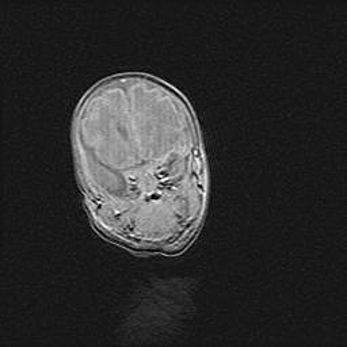

Открытая гидроцефалия.

Возраст: 9 месяцев 12 дней

Вес: 6800 г

Пол: мужской

Окружность головы: 41,5 см

Срок гестации: 28 недель

Гидроцефалия головного мозга у новорожденных имеет характерный признак: опережающий рост окружности головы приводит к визуально хорошо определяемой гидроцефальной форме сильно увеличенного в объёме черепа. Детские неврологи определяют следующие симптомы гидроцефалии у грудничков: выбухающий напряжённый родничок, частое запрокидывание головы, смещение глазных яблок к низу.